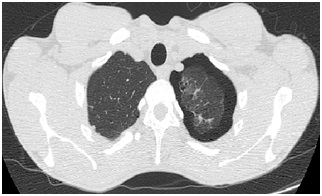

11. Bilgisayarlı

Toraks Tomografi kesiti altta verilen hastada diyafram patolojisi ne olabilir?

a)

Bochdalek

hernisi

b)

Morgagni

c)

Sliding

herni

d)

Paraözofageal

e)

Mikst